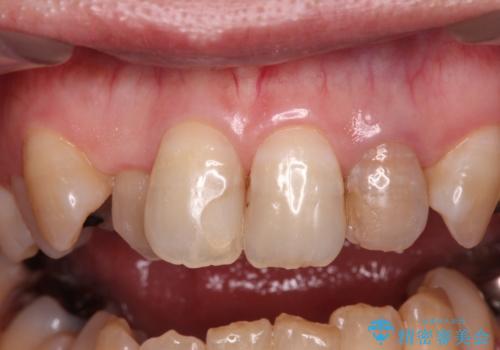

- 20年以上前に神経を取り除いた前歯の変色が気になるとのことで来院された患者様です。

レントゲン写真より、歯根の炎症が認められなかったため、ファイバーコアによる土台築製後、オールセラミッククラウンにて補綴することとしました。

また、真ん中の前歯はコンポジットレジンによる修復跡が目立っており、合わせてオールセラミッククラウンにて治療することとしました。

歯に独特の縞模様があり、さらに特徴的な色合いであったため、コンポジットレジンによる修復では対応が困難でした。